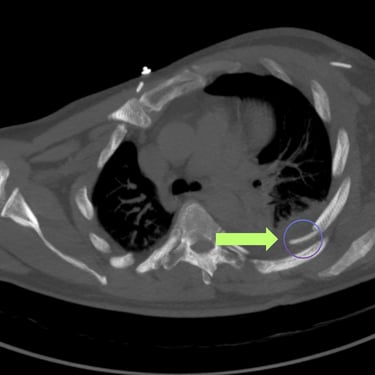

Hidrocefalia y Disfunción de Derivación: Colocación de Derivación Ventrículo-Pleural

La hidrocefalia puede complicarse cuando la derivación ventrículo-peritoneal deja de funcionar correctamente, produciendo aumento de la presión intracraneal y síntomas como cefalea, vómitos, somnolencia o deterioro neurológico. Cuando el peritoneo deja de ser una opción viable debido a infecciones, cirugías previas o mala absorción, se considera la derivación ventrículo-pleural como alternativa efectiva. Este procedimiento permite redirigir el líquido cefalorraquídeo hacia la cavidad pleural, donde puede ser absorbido adecuadamente. La intervención oportuna restablece el drenaje del LCR, reduce la presión intracraneal y mejora el pronóstico del paciente, siendo una solución segura en casos de disfunción peritoneal.